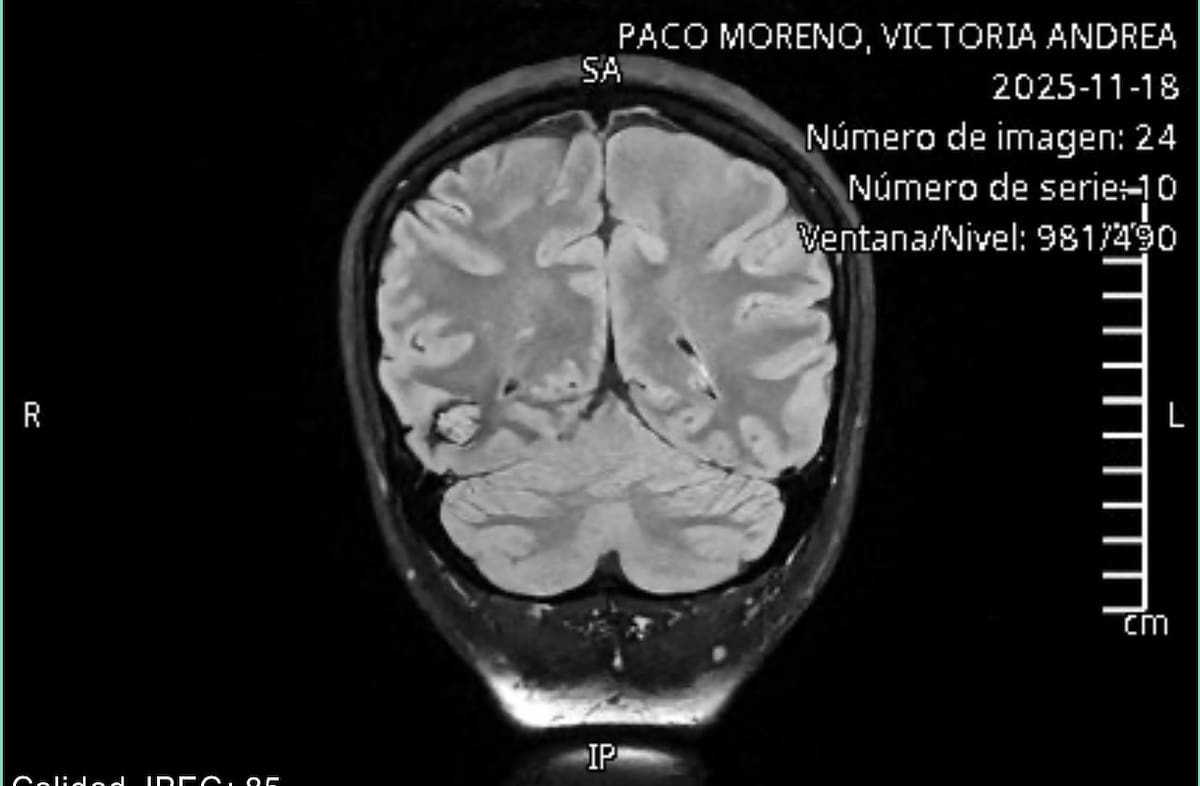

Ensenada BC.- Victoria Andrea Paco Moreno de 22 años de edad, fue diagnosticada hace dos meses con malformaciones en las arterias del cerebro, por lo que es necesario que se someta a una cirugía de alto riesgo.

La joven originaria de Ensenada y estudiante de producción musical, ha sufrido tres crisis convulsivas a causa de epilepsia secundaria, por lo que los médicos le han informado que requiere una craneotomía, una cirugía de cráneo abierto para evitar que su salud empeore.

Me dijo el neurólogo que la única forma de tratar este cavernoma es por medio de una craneotomía, que consiste en extraer parte del cráneo para poder acceder al cerebro, primero me canaliza al neurocirujano para una valoración y me dice que efectivamente es la mejor forma de tratarlo, obviamente uno cuando escucha este proceso se intimida porque te tienen que abrir la cabeza”

Explicó.